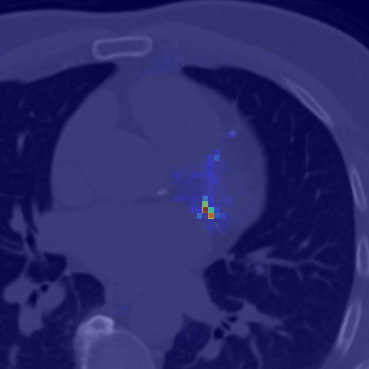

Coronary artery disease (CAD), one of the leading causes of mortality worldwide, necessitates effective risk assessment strategies, with coronary artery calcium (CAC) scoring via computed tomography (CT) being a key method for prevention. Traditional methods, primarily based on UNET architectures implemented on pre-built models, face challenges like the scarcity of annotated CT scans containing CAC and imbalanced datasets, leading to reduced performance in segmentation and scoring tasks. In this study, we address these limitations by incorporating the self-supervised learning (SSL) technique of DINO (self-distillation with no labels), which trains without requiring CAC-specific annotations, enhancing its robustness in generating distinct features. The DINO-LG model, which leverages label guidance to focus on calcified areas, achieves significant improvements, with a sensitivity of 89% and specificity of 90% for detecting CAC-containing CT slices, compared to the standard DINO model's sensitivity of 79% and specificity of 77%. Additionally, false-negative and false-positive rates are reduced by 49% and 59%, respectively, instilling greater confidence in clinicians when ruling out calcification in low-risk patients and minimizing unnecessary imaging reviews by radiologists. Further, CAC scoring and segmentation tasks are conducted using a basic UNET architecture, applied specifically to CT slices identified by the DINO-LG model as containing calcified areas. This targeted approach enhances CAC scoring accuracy by feeding the UNET model with relevant slices, significantly improving diagnostic precision, reducing both false positives and false negatives, and ultimately lowering overall healthcare costs by minimizing unnecessary tests and treatments, presenting a valuable advancement in CAD risk assessment.